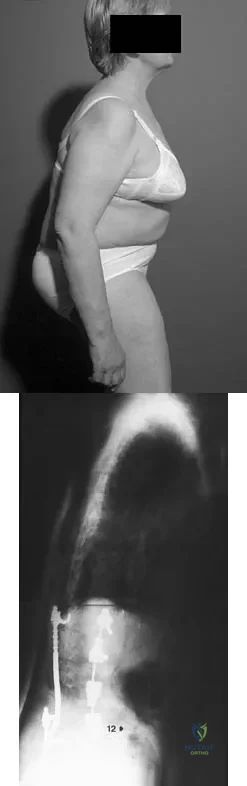

Based on the findings shown in Figures 22a and 22b, corrective surgery to obtain maximal safe correction and optimal instrumentation fixation should be performed at which of the following locations?

Detailed Explanation